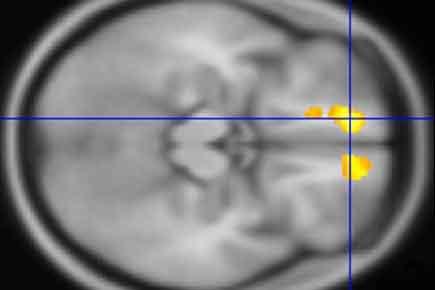

Using MRIs, researchers at Washington University School of Medicine in St. Louis have identified areas in the brains of children with Tourette's syndrome that appear markedly different from the same areas in the brains of children who don't have the neuropsychiatric disorder.

In the largest study of its kind, the researchers conducted MRI scans at four U.S. sites to study the brains of 103 children with Tourette's and compared them with scans of another 103 kids of the same age and sex but without the disorder. The scans of the children with Tourette's revealed significantly more gray matter in the thalamus, the hypothalamus and the midbrain than in those without the disorder.

The gray matter is where the brain processes information. It's made up mainly of cells such as neurons, glial cells and dendrites, as well as axons that extend from neurons to carry signals.

In kids with Tourette's, the researchers also found less white matter around the orbital prefrontal cortex, just above the eyes, and in the medial prefrontal cortex, also near the front, than in kids without the condition.

White matter acts like the brain's wiring. It consists of axons that -- unlike the axons in gray matter -- are coated with myelin and transmit signals to the gray matter. Less white matter could mean less efficient transmission of sensations, whereas extra gray matter could mean nerve cells are sending extra signals.